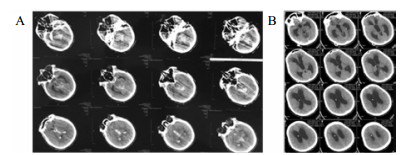

1 资料与方法病例1, 女,24岁,2015年12月以“脑干出血破入脑室术后1年,脑积水V-P分流术后”入院。入院时为植物状态,GCS 8分,双瞳孔3.0 mm, 对光反应灵敏,双侧巴氏征阳性;V-P分流调压阀压力为1.0(Medtronic, Minnesota, USA),储液囊外接引流管,压力为外耳道连线上方10 cmH2O (1 cnH2O = 0.098 kPa)。诊断为:脑干出血术后、脑积水、永久性植物状态(图 1)。

| A:2014年12月2日CT;B: 2015年12月8日入院CT,分流压力为1.0 图 1 病例1 CT |

将分流管压力降为0.5后的第6天,该患者复查头颅CT和意识水平均无明显改变;后经分流储液囊穿刺脑脊液外引流,每日引流量150 mL,持续10 d,仍无明显改变。再将脑脊液外引流量增至300 mL/d,患者行为学稍有变化,开始出现刺激后头部转动、手部摸索活动,眼球能视觉追踪。复查头颅CT示脑室形态略缩小。因此,在此基础上再次手术将分流管由原来的抗虹吸可调压管更换为非抗虹吸可调压管,压力设为1.0。患者意识水平进一步改善,术后第4天复查CT示脑室较前缩小(图 2),其大小形态接近正常。随访一年,患者生活能自理,E-GOS 5分。

| 图 2 病例1更换分流管后第4天头颅CT |